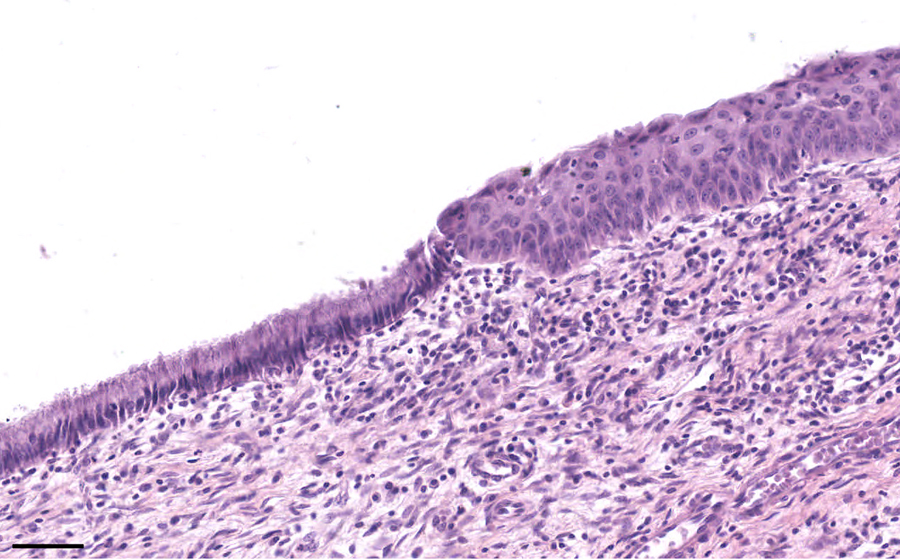

Image 22: Cervix - squamous cell carcinoma

Histologic section of cervix from a patient with cervical squamous cell carcinoma.

Sections of normal cervix